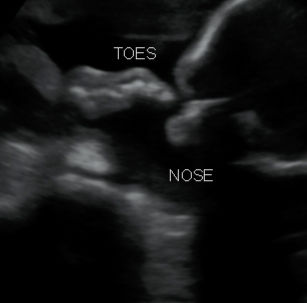

26 Weeks 1 Day Pregnant

26 Weeks 3 Day Pregnant

Look at these beautiful face pictures, even with an Anterior Placenta!